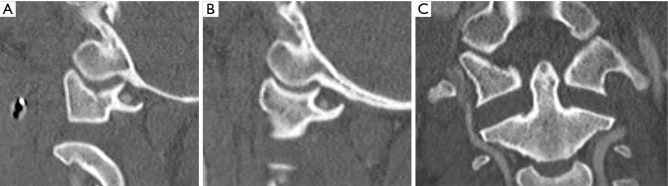

On arrival, he had elevated troponins but otherwise normal laboratory workup and electrocardiogram (EKG). He remained hypotensive throughout his initial presentation. He had multiple facial lacerations. A reliable neurologic exam could not be obtained due to the patient’s intubated and sedated status, however bulbocavernosus reflex was intact, reflexes were normal and the patient did not demonstrate evidence of spinal or neurogenic shock. Radiographs revealed a right Arbeitsgemeinschaft für Osteosynthesefragen (AO) Type C Pilon fracture, a right cuboid fracture, and a left anterior hip dislocation. CT of the head revealed bilateral mandibular fractures, and a right lateral pterygoid fracture, without evidence of intracranial hemorrhage or embolus. CT of the full spine revealed distraction of the C1-C2 articulation without associated fracture, and without clear disruption or distraction of the O-C1 joint (Figure 1A-1C). The patient was placed in a Miami J cervical collar (C-collar). Due to persistent hemodynamic instability with no obvious source, he was taken to the operating room (OR) for emergent exploratory laparotomy with general surgery, which ultimately did not reveal any intraabdominal hemorrhage or injury. His left hip was closed reduced while on the operating table after the abdomen was closed.

Figure 1.

Injury cervical spine CT scan showing (A) subtle subluxation of the left occipitocervical junction with impaction of the O-C1 facet joint and distraction of the atlantoaxial interval, (B) normal appearing right occipitocervical junction, and (C) distraction of the atlantoaxial interval. CT, computed tomography; O-C1, atlanto-occipital.